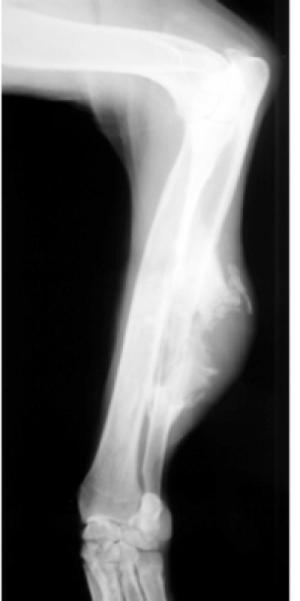

A radiograph of a dog’s leg with a cancerous lesion. (Credit: Image courtesy of American Society of Anesthesiologists (ASA))